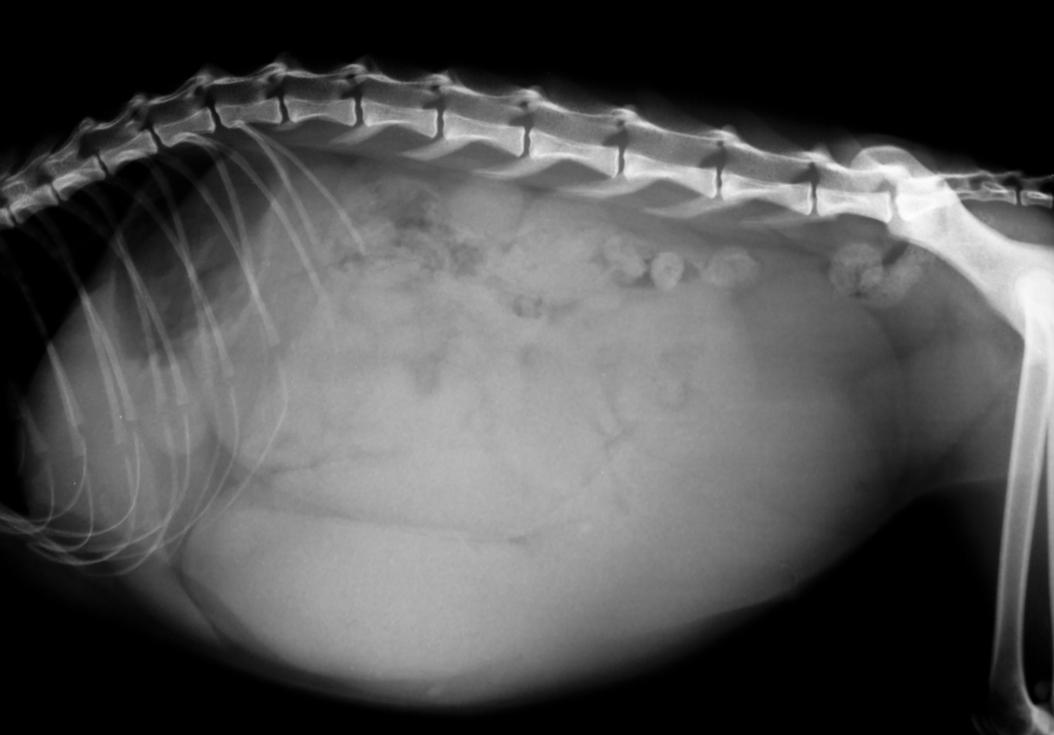

Radiographic and ultrasonographic appearance of pyometra with How Long Does Pyometra Last In Cats Routine spay surgeries typically require very little hospitalization time however, cats who undergo surgery to treat a pyometra are. How long can a cat live with pyometra? Recovery time can vary depending on the individual cat. Once the infection has become established, if the cat does not receive prompt treatment, the cat will deteriorate very quickly. How long can a. How Long Does Pyometra Last In Cats.